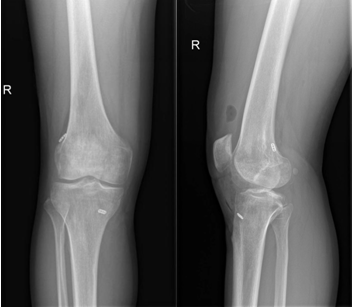

近日,一名31岁男性因打篮球扭伤致“右膝关节疼痛伴行走不稳半年”入院,术前诊断:前交叉韧带部分断裂。考虑患者年轻且有较高的运动恢复需求,在骨科病院刘时璋主任医师的指导下,由冯敏副主任医师主刀完成欧美视频

首例关节镜辅助下前交叉韧带损伤“保残+全内”重建术。患者第二日即下地活动,第三天顺利出院。

ACL的保残重建具有有效促进ACL移植物血管再生,促进损伤ACL本体感觉的恢复,以及防止ACL术后隧道扩大等多种技术优势。而ACL的全内重建技术是国际上新近发展出现的另一项新技术,相比传统方法,它仅需获取自身单根肌腱,而且所需长度远小于传统重建方法。另外,此技术保留了更多的骨皮质及骨膜,术后疼痛更少,腱骨愈合更佳,同时有效降低了术后感染风险,避免了传统方式界面螺钉对肌腱的切割作用。